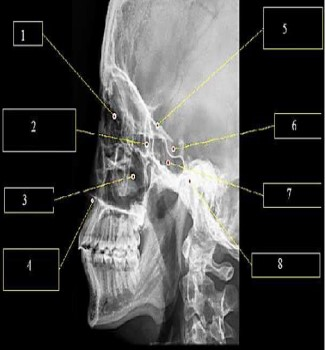

A imagem abaixo representa uma radiografia de crânio perfil.

A estrutura apontada pelo número 6 indica: